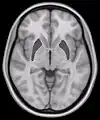

Coronal section of brain through intermediate mass of third ventricle. (Putamen labeled at top.) | |

Human brain frontal (coronal) section Horizontal slice of MRI-image showing the putamen. The other nuclei of the basal ganglia (caudate nucleus and globus pallidus) can be seen as well.

Horizontal slice of MRI-image showing the putamen. The other nuclei of the basal ganglia (caudate nucleus and globus pallidus) can be seen as well. Putamen